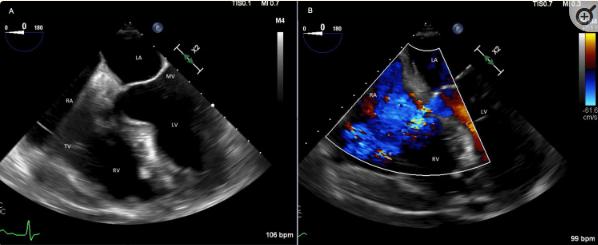

在TEE期间,通过三尖瓣上方的采样可以看到先前描述的TR包膜。该反流射流起源于左室,进入RA(图2)。观察到轻度TR,这证实了先前在TTE上注意到的TR实际上是从左室到左室的VSD反流,称为Gerbode缺陷。影像学检查未见明显赘生物或主动脉根部脓肿。

图2、Gerbode缺损的经食管观察。图A为四腔面,Gerbode缺损位于三尖瓣上方。B组多普勒彩色波通过Gerbode缺损,从左心室进入右心房